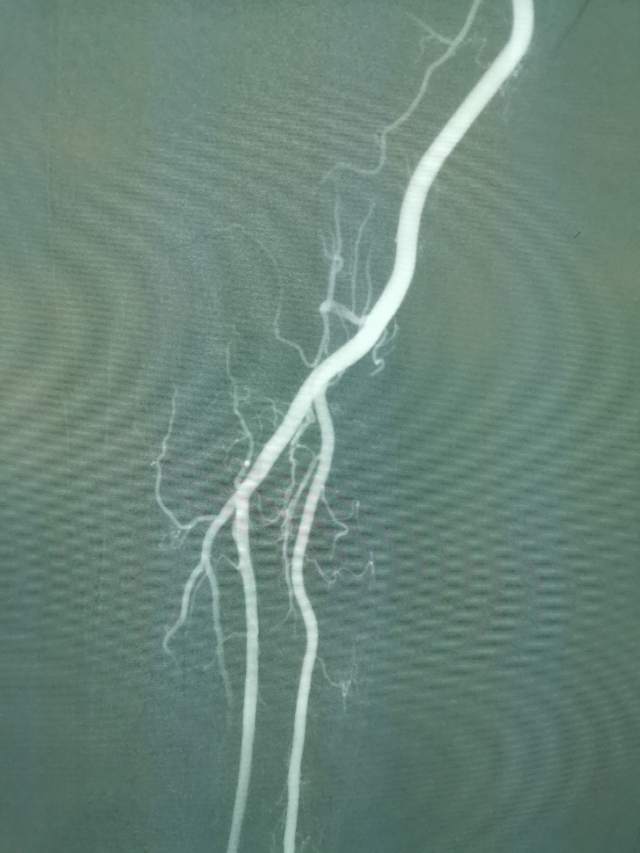

鉴于老人家体质虚弱,走路不方便,疫情期间,家人又不方便陪同,我们采用最微创的远侧桡动脉入路为老人家做了进一步检查,血管真的很扭哈,老人家也听不清楚,检查期间动来动去的,结果发现:下水道(深浅静脉系统有血栓堵塞)不通畅哦,次日给予了药物调整。治疗3天后,老人家听力明显改善,可以和医生自由交流,下床走路也如履平地,完全换了一个人哈~~~